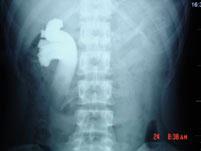

问题 男,20岁,右腰部胀痛不适,MR如图示,下列说法正确的是 ( )

选项 A、考虑为右侧腔静脉后输尿管 B、考虑为右侧输尿管自身的扭曲 C、右侧输尿管上段扩张积水 D、右侧输尿管走行异常,呈“S”形向中线移位 E、右侧肾盂积水

答案 ACDE